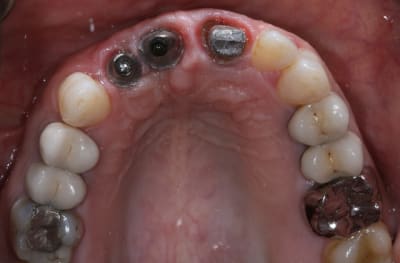

Patiente de 30 ans suite à parodontite a perdu 11-12 avec grosse perte osseuse.

Bon voila le scann de 11-12 (pas 21-22 comme noté)

C'est vrai que j'ai à mort d'os en épaisseur.

Le manque est surtout en hauteur.

Dans tous les cas je refais 21 en même temps.

Bon ben j'ai implanté avant d'avoir refait la 21. Du coup j'ai mésialé la pose de 11 pour compenser la distalisation de 21.

Au final je n'ai pas fait de greffe osseuse... et j'ai réalisé une technique de rouleau sur 11-12 mais je reste un peu court à mon goût.

J'ai mis en place des transitoires sur 11-12-21 pour temporiser 3 mois pour voir la maturation des tissus mous.